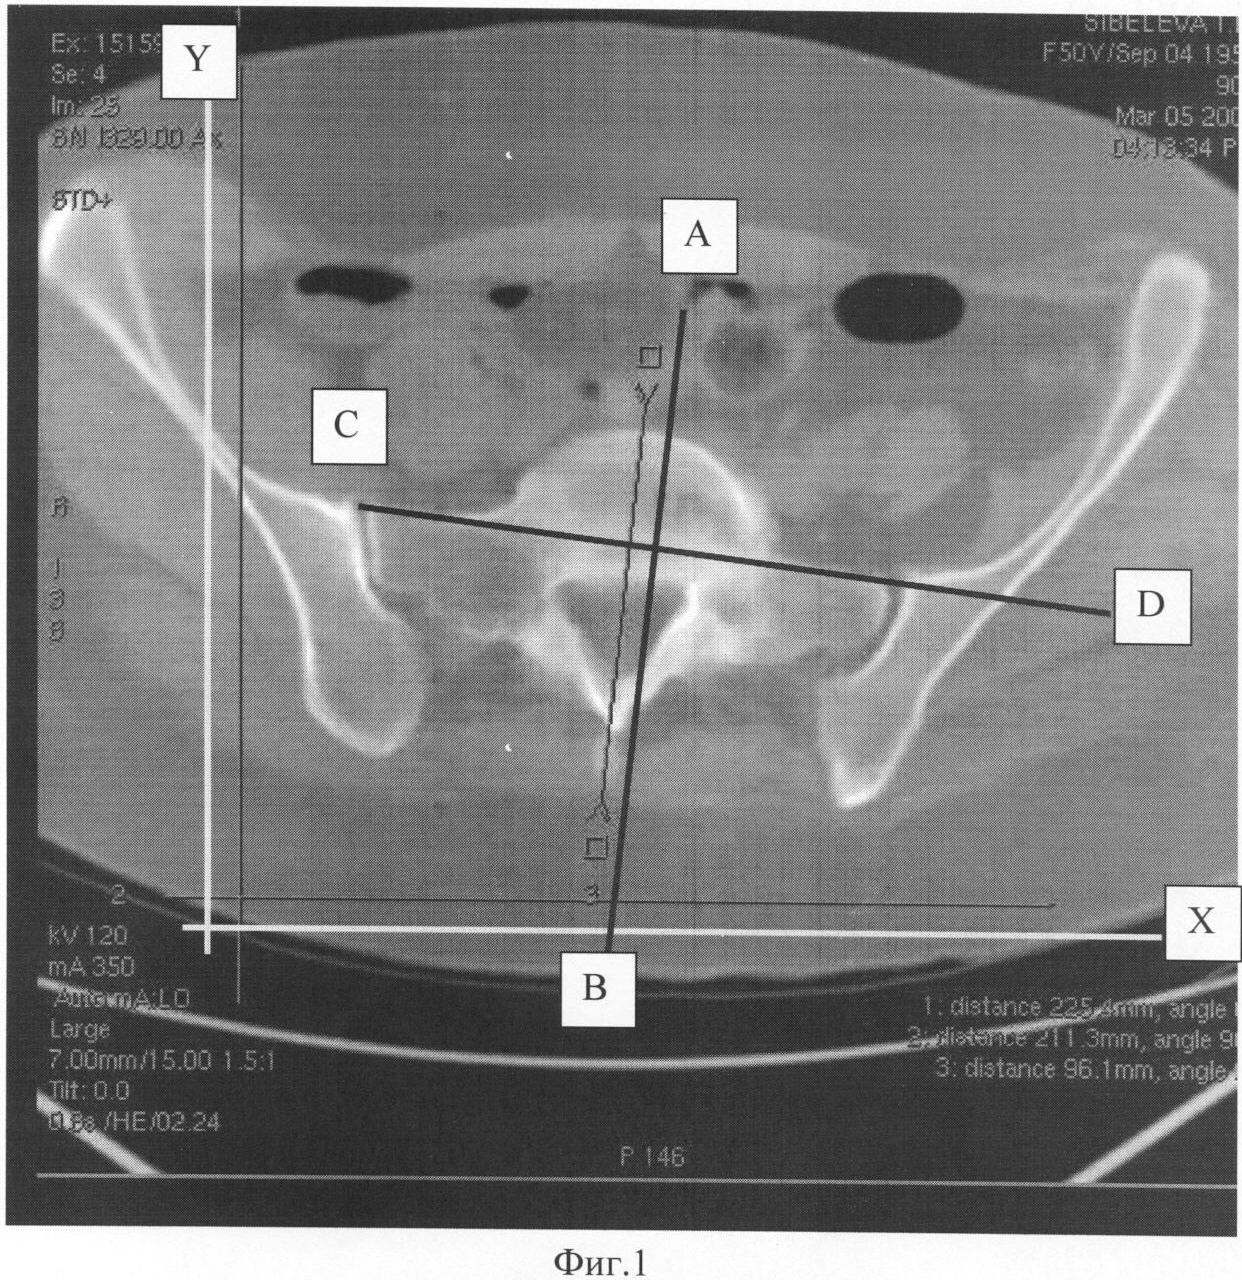

На фиг.1 представлен КТ срез на уровне подвздошно-крестцовых сочленений.

Больному тяжелой формой коксартроза в диагностическом плане выполняют КТ таза на уровне подвздошно-крестцовых сочленений и КТ на уровне тела Тh3, затем на КТ срезе на уровне подвздошно-крестцовых сочленений проводят линию CD во фронтальной плоскости через передние края подвздошно-крестцовых сочленений (фиг.1) и линию АВ в сагиттальной плоскости через середину остистого отростка и тел S1-S3 (фиг.1), а на КТ срезе на уровне тела Тh3 проводят линию CD во фронтальной плоскости через передние края поперечных отростков тела Тh3 (фиг.2) и линию АВ в сагиттальной плоскости через середину остистого отростка и тела Тh3 (фиг.2), после чего измеряют величины углов, полученных при пересечении проведенных линий на уровне подвздошно-крестцовых сочленений и на уровне тела

Тh3 с линиями оси координат (X и Y), восстановленными на КТ срезах при помощи компьютерной программы КТ.

На томограмме на уровне тела Тh3 рентгенометрически определена величина ротации тела Тh3 и правой половины плечевого пояса кпереди и влево на 2°. На томограмме на уровне подвздошно-крестцовых сочленений определена величина ротации таза кпереди и влево на 8°. Разница величин ротации на уровне подвздошно-крестцовых сочленений и на уровне тела Тh3 составила 6°.